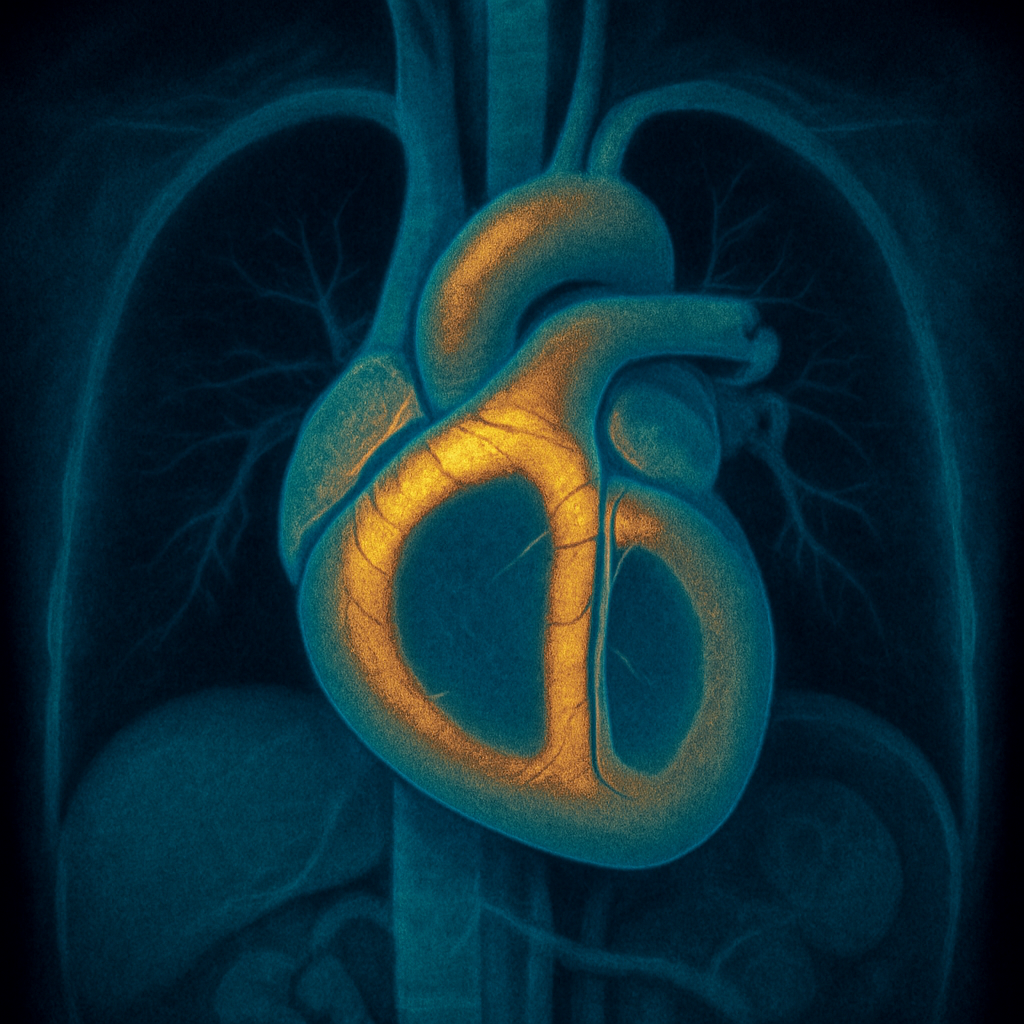

AI-generated comprehensive cardiac phantom with all four chambers, valves, coronary arteries, great vessels, pericardium, and surrounding structures for multi-modality cardiac imaging training

Modalities: CT MRI ULTRASOUND PET SPECT DIGITAL RADIOGRAPHY

Images: 32

Structures: 24

Compatible Instruments: 19